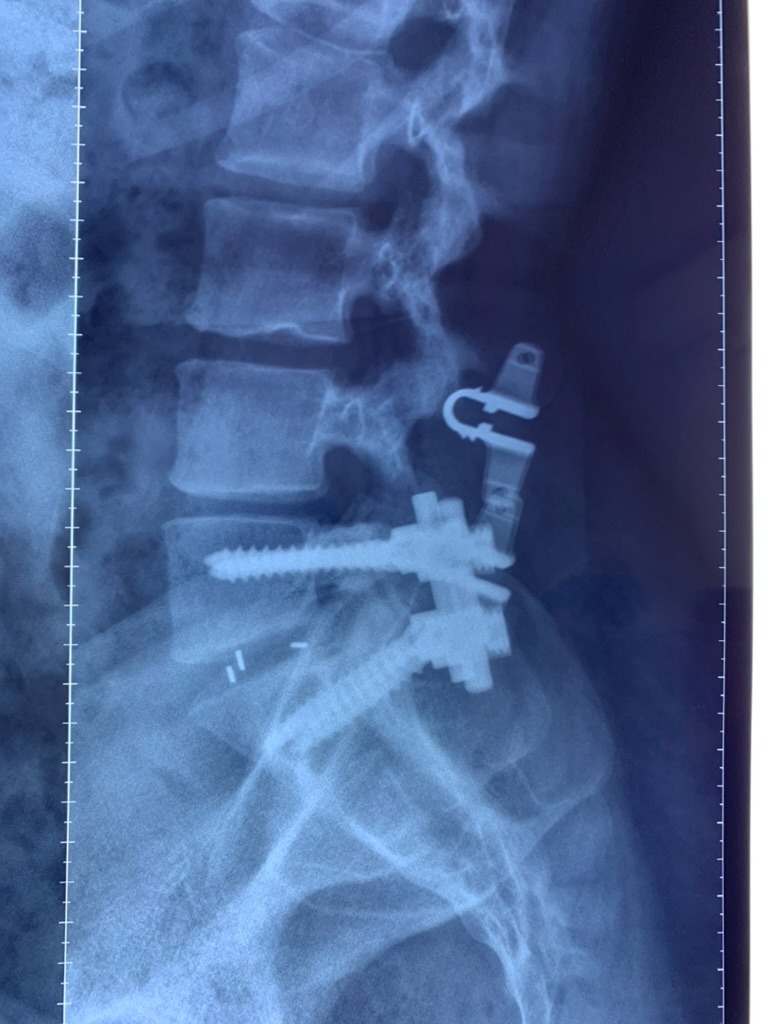

SURGERIES

RESULTS